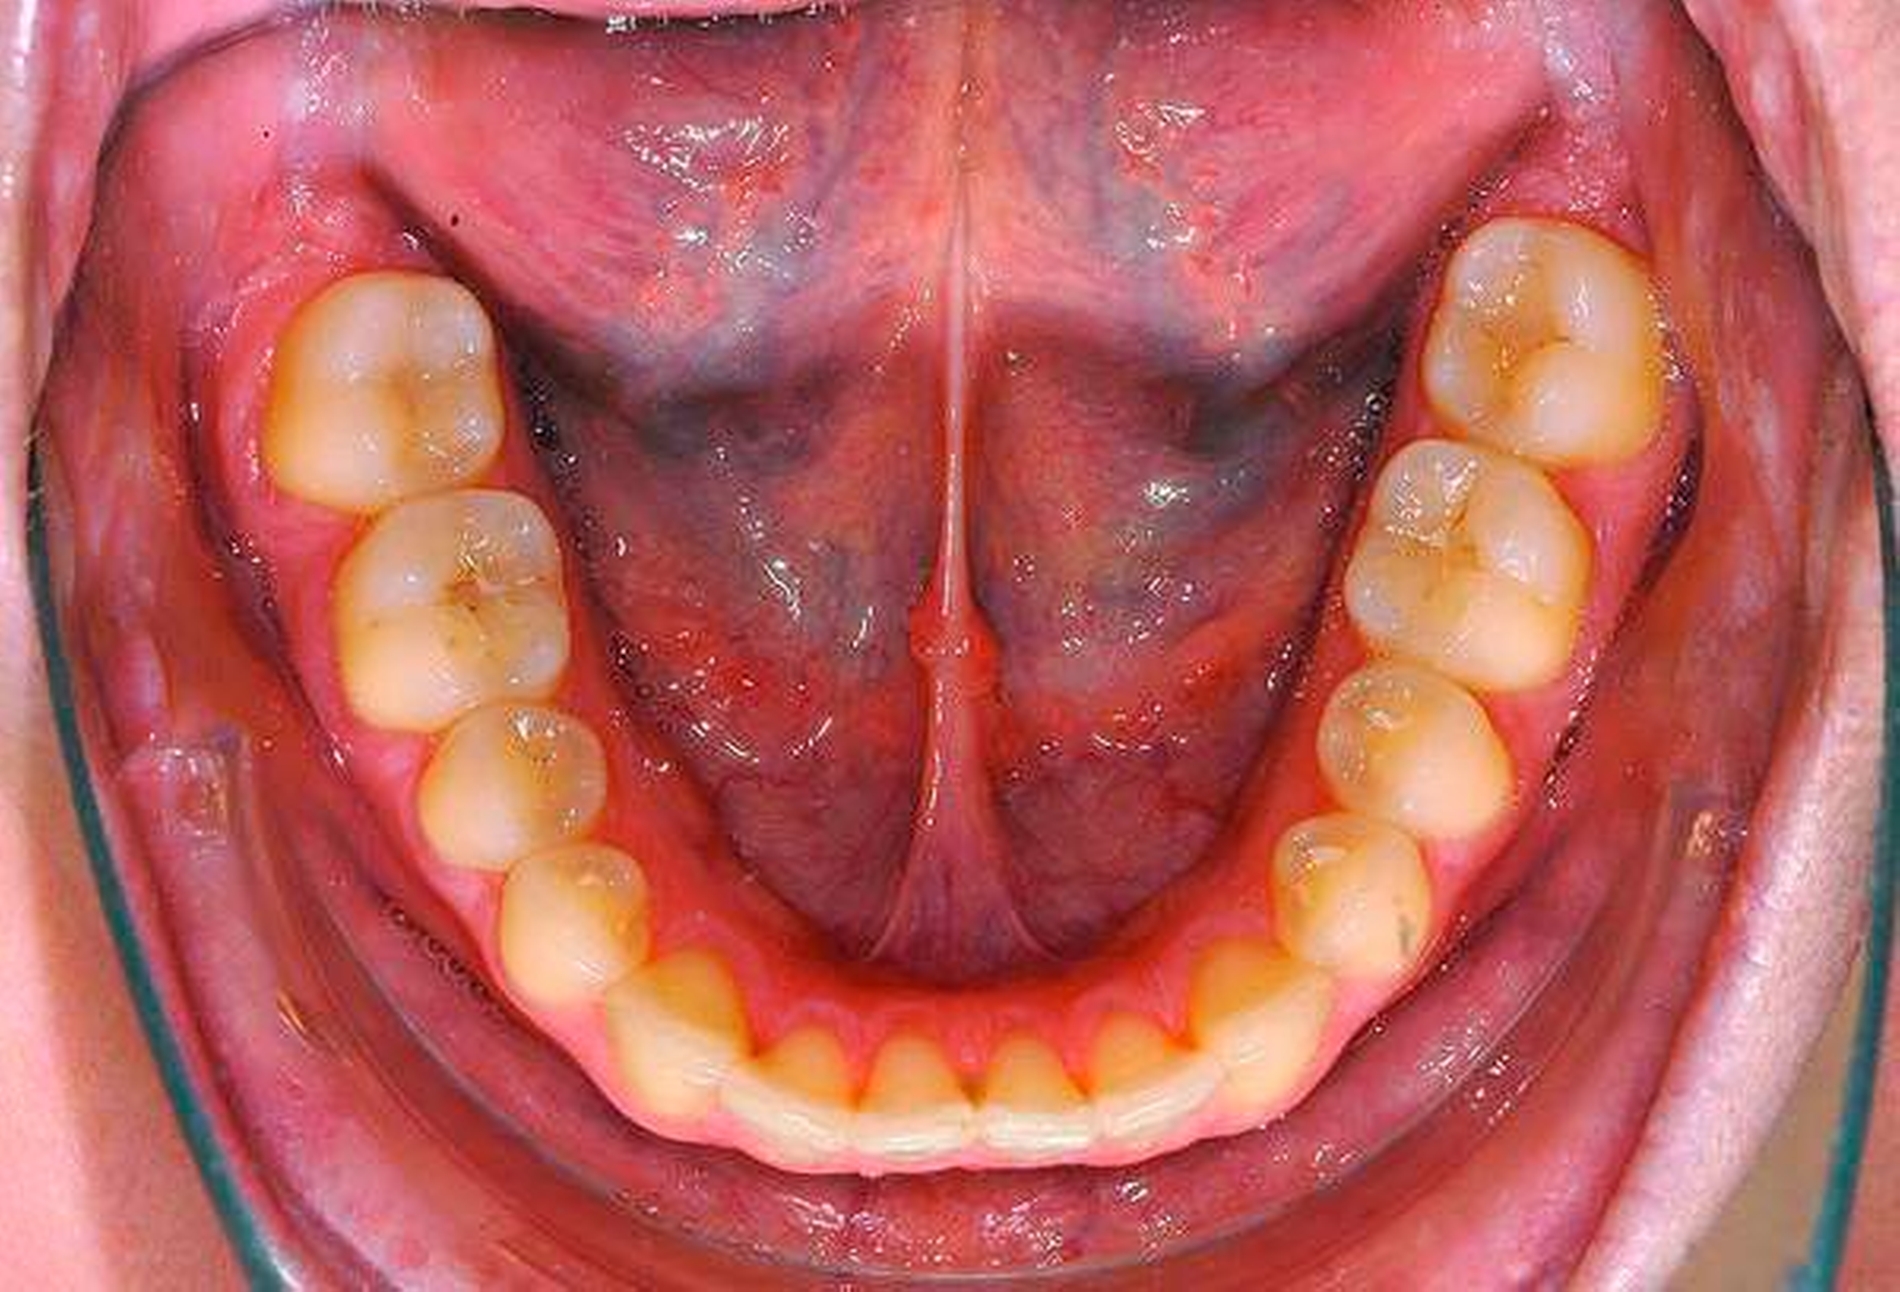

Die Entfernung aller Weisheitszähne wurde schließlich nach einem weiteren frustranen Extraktionsversuch unter Lokalanästhesie in Intubationsnarkose durchgeführt, der postoperative Verlauf gestaltete sich komplikationslos, auffällige Blutungen traten nicht auf (Abbildungen 2 und 3).